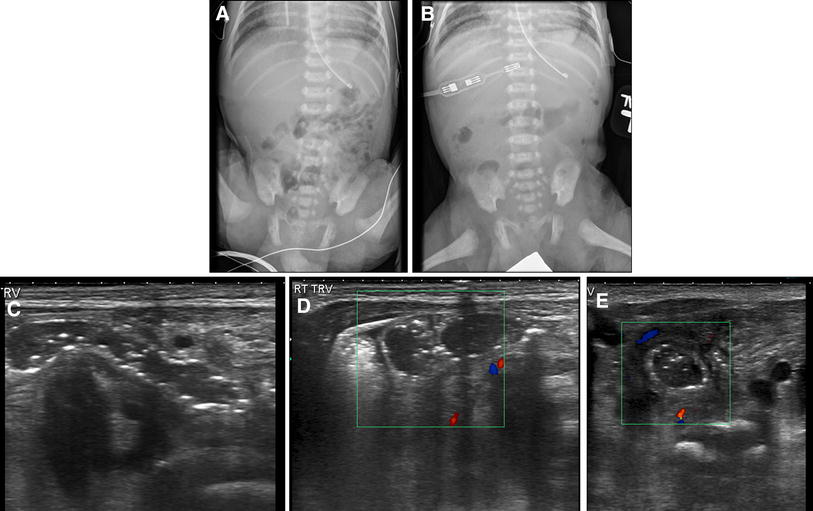

Prospective evaluation of the impact of sonography on the management Proximal Jejunostomy 14 jejunal mucosa is “leaky” and rapid sodium fluxes occur across it. Gastrojejunostomy (gj) is a surgical procedure in which an anastomosis is created between the stomach and the proximal loop of the jejunum. If less than 100 cm of jejunum remains proximal to a jejunostomy the patient may lose more fluid than is taken by mouth. Jejunostomy is a. Proximal Jejunostomy.